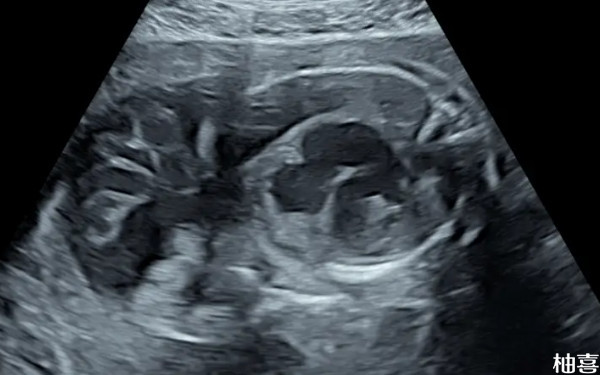

试管胚胎d7是什么意思啊?

试管胚胎d7一般是指已经发育了7天的生殖细胞,该阶段的胚胎一般为囊胚,拥有100个细胞以上的细胞团相对d3胚胎,移植成功率会更高一些,可以达到50%-60%,但具体是否能怀孕成功,还需要考虑到心理状态,毕竟长期处于紧张、焦虑、抑郁等不良情绪中,人体的内分泌系统会受到干扰,激素水平失衡,这对卵子的排出、胚胎的着床等环节都会产生不利影响。